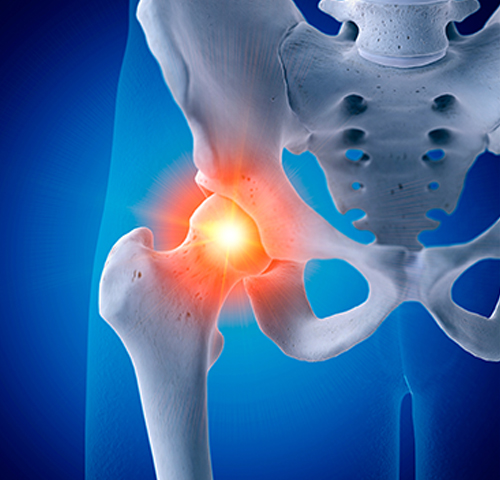

무혈성괴사

혈액순환장애로 넓적다리뼈 윗부분이 썩고 고관절이 무너지는 증상으로

조기진단이 매우 중요하며 해당부위 통증 발생 시 상담이 필요합니다.